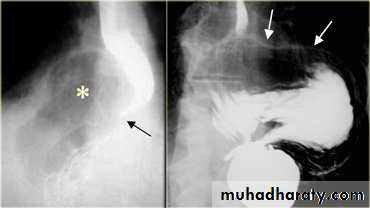

On the far left a traction diverticulum (arrow) due to hilar granulomatous disease. Calcified adenopathy (asterisk). In the middle a pulsion diverticulum (arrow) due to high intra luminal pressure.On the right multiple pulsion diverticula (arrows)